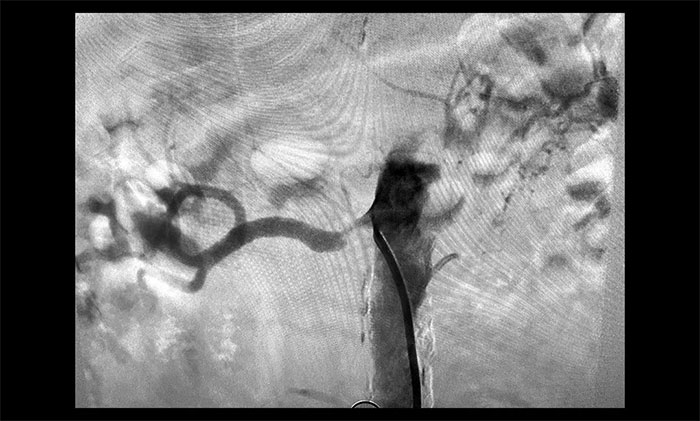

席刚明教授进一步行DSA脑血管造影检查,患者脑动脉多发性狭窄(右侧颈内动脉、大脑中动脉、基底动脉等),左侧颈总动脉闭塞,右侧椎动脉闭塞,右侧肾动脉重度狭窄(狭窄率大于70%),左侧肾动脉闭塞。

▲ 患者右侧肾动脉重度狭窄,左侧闭塞

结合检查结果,席刚明教授团队对病情开展审慎分析评估。患者近期血压居高不下,视力模糊加重,考虑病情与肾血管性高血压有关。其一侧肾动脉已闭塞,左肾萎缩,左肾几乎失去功能。如不及时治疗,不仅血压难以控制,还可能导致脑血管病再发及肾功能进行性恶化,甚至发生肾衰竭等严重并发症。